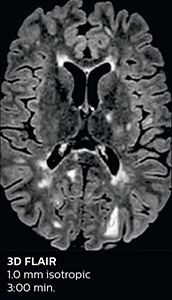

The choice for two Elition scanners was not made lightly. Dr. Savatovsky and his team compared devices from different vendors before making the decision. “Part of this process was our assessment of the image quality of different devices. We put together a list of sequences with detailed requirements, including limited acquisition times, to allow a fair comparison. We even put the same volunteer in each scanner. Our assessment was that the image quality was better with the Elition scanner. Compressed SENSE or Multiband SENSE was used for almost every sequence, and I think this helped a lot to maintain a great image quality in the shorter acquisition time.”

According to Dr. Savatovsky, Ingenia Elition has an impact in virtually all examinations. “We can either make the scanning faster compared to our older Ingenia 3.0T, or we save enough time so that we can add sequences we wouldn’t perform otherwise, or increase resolution. So, I think it has benefits for most of our patients.” “Some routine exams that we use every day have been shortened since we started using Elition. For example, we now use mostly a comprehensive stroke protocol (high b-value diffusion, fast 3D FLAIR, TOF, supra-aortic vessels angiography, SWIp, T1 post gad) that lasts 10 to 11 minutes, but our fast stroke protocol takes only 7 minutes. Our routine IAC needs about 10 minutes scan time and our comprehensive brain MS examination requires no longer than 13 minutes of scan time. Our ability to reduce acquisition times of most sequences helps to shorten total examination times, which in turn helps us to increase the number of patients we scan per day. “The main breakthrough for us was that Compressed SENSE and Multiband SENSE have allowed us to accelerate our examinations. Alternatively, we can invest the time gained in obtaining higher spatial resolution to see more details, or we can add additional sequences,” says Dr. Savatovsky. “That’s a big improvement from what we did before.”

A two year follow-up scan of a CPA meningioma using both Ingenia 3.0T without CS and Ingenia Elition 3.0T with Compressed SENSE allows for a nice comparison to demonstrate the protocol improvements achieved on the Elition: 3D FLAIR has a shortened scan time, improved SNR and still the same spatial resolution. BrainView (3D T1 TSE) has improved spatial resolution and SNR with shortened scan time. For 3D T2 Drive the spatial resolution has been improved. 3D THRIVE used to have an interpolated 0.8 mm slice thickness, but true thickness at 1.6 mm, so that axial slices displayed a decent quality, but reformats were suboptimal. Compressed SENSE is used on Elition to improve spatial resolution and reduce the non-interpolated slice thickness to allow smoothly reformatted images. Total scan time (adding SmartBrain and an additional b2000 diffusion) was 13:19 on Ingenia, and is now reduced to 10:42 on Ingenia Elition.

Ingenia 3.0T (without Compressed SENSE)

3D FLAIR 1.0 x 1.0 x 1.0 mm* 4:24 min.

3D TSE T1w 1.0 x 1.0 x 1.2 mm* 2:40 min.

3D T2w Drive 0.8 x 0.8 x 1.0 mm* 3:05 min.

3D T1w THRIVE 0.8 x 0.8 x 1.6 mm* 1:30 min.

Ingenia Elition 3.0T with Compressed SENSE

3D FLAIR 1.0 x 1.0 x 1.0 mm* 2:50 min.

3D TSE T1w 1.0 x 1.0 x 1.0 mm* 2:10 min.

3D T2w Drive 0.7 x 0.7 x 0.7 mm* 2:52 min.

3D T1w THRIVE 0.7 x 0.7 x 0.8 mm* 1:30 min.

*true voxel size, without interpolation